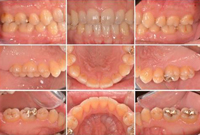

STEP02検査①【口腔内の写真撮影】

診療前の状況を視覚的に確認できるように、デジタルカメラで口の中の写真撮影を行います。

また、咬合学や矯正学の観点から口腔内だけではなく、顔の写真も撮影致します。これは、左右の筋肉の対称性や噛み合わせの高さの診断に使用します。 -